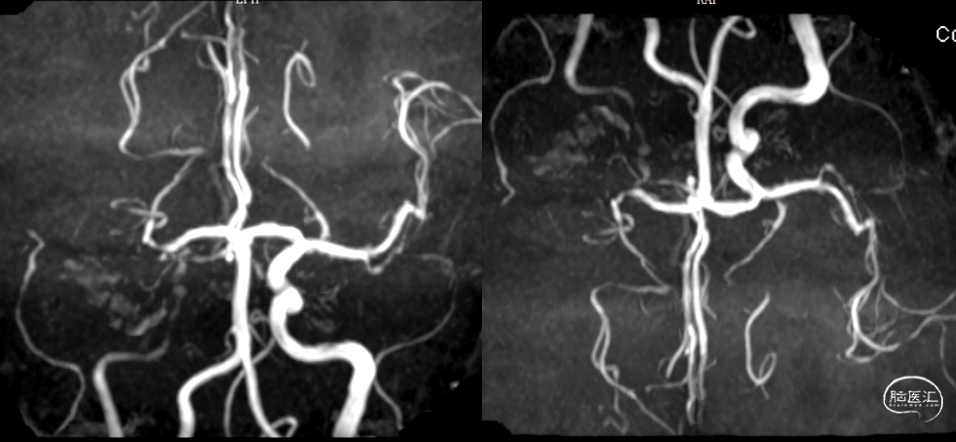

头颅MRA:右侧颈内动脉闭塞。

右侧大脑中动脉起始部闭塞,左侧前交通开放,左侧大脑前动脉通过软膜支代偿,大脑后动脉通过软膜支代偿,侧支代偿可,考虑粥样硬化合并急性闭塞的可能。